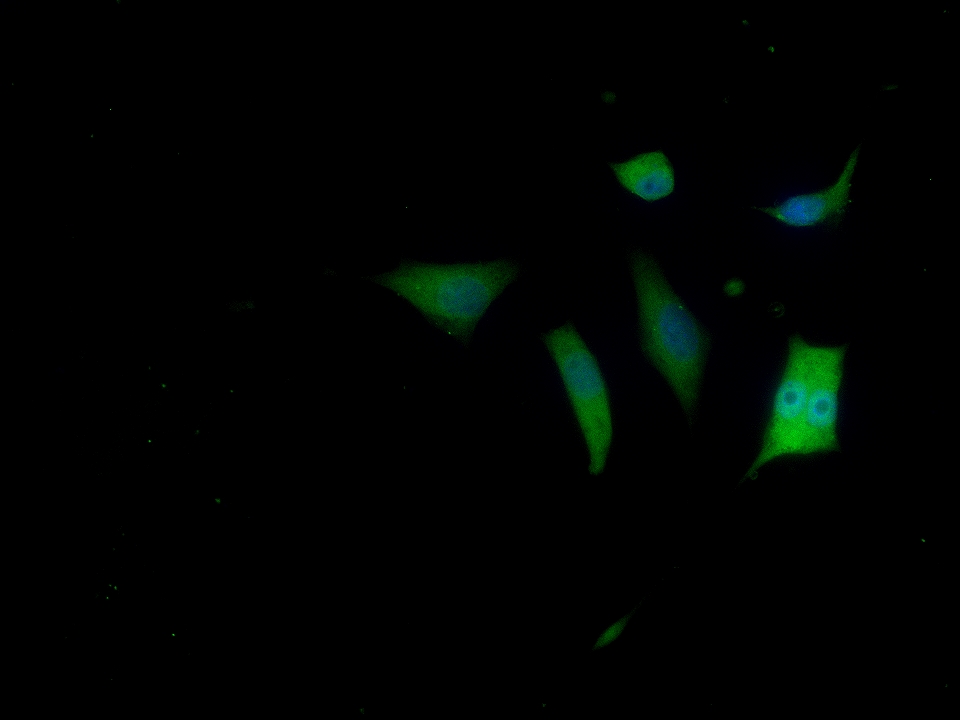

產(chǎn)品圖片

SH-SY5Y cell; 4% Paraformaldehyde-fixed; Triton X-100 at room temperature for 20 min; Blocking buffer (normal goat serum, C-0005) at 37°C for 20 min; Antibody incubation with (FGF1) polyclonal Antibody, Unconjugated (bs-0229R) 1:100, 90 minutes at 37°C; followed by a conjugated Goat Anti-Rabbit IgG antibody at 37°C for 90 minutes, DAPI (blue, C02-04002) was used to stain the cell nuclei.